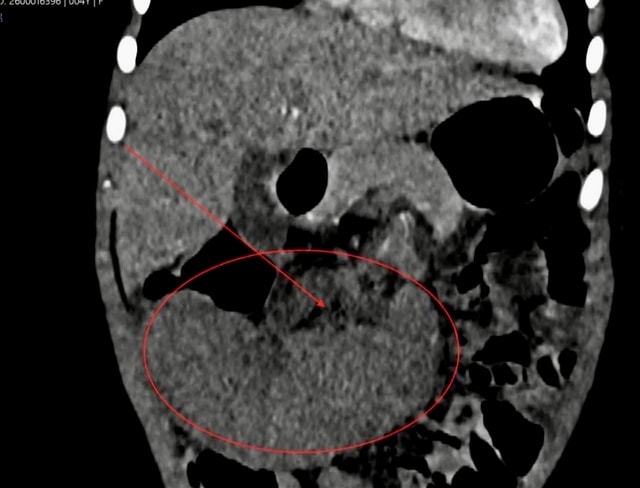

Hình ảnh phần lách của bệnh nhi lớn, nằm ở vị trí bất thường, lách không tưới máu...

Các bác sĩ tiến hành khám và cho bệnh nhân thực hiện các xét nghiệm. Kết quả phát hiện phần lách của bệnh nhi lớn, nằm ở vị trí bất thường, lách không tưới máu (nhồi máu lách), toàn bộ lá lách bị thiếu oxy và dưỡng chất do mạch máu nuôi dưỡng (động mạch lách) bị tắc nghẽn, dẫn đến mô lách bị hoại tử.